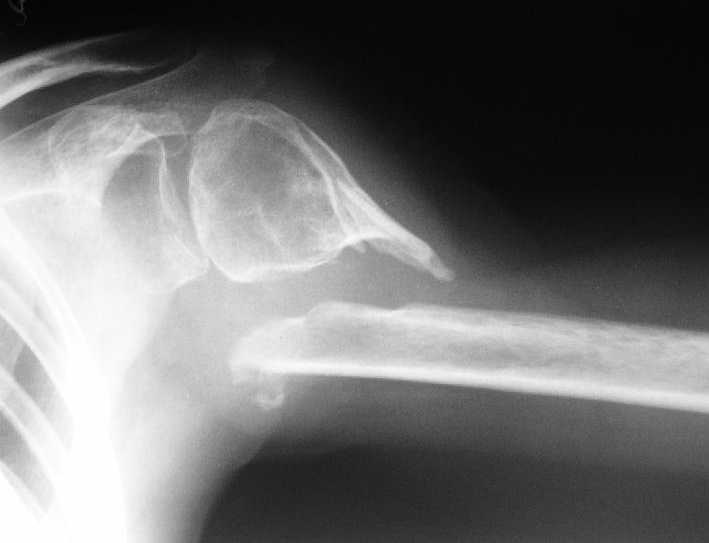

Несращение плеча, деформация головки

Здравствуйте уважаемые коллеги.Помогите, пожалуйста, определиться с тактикой.Больная 40 лет, множественная травма в июне 2007 года. Лечилась в городской больнице.

Повреждение проксимального отдела плеча вели консервативно в гипсовой повязке. В настоящее время больную беспокоят боли в области плечевого сустава, слабость верхней конечности. Амплитуда движений в плечевом суставе в пределах 30-40 градусов. Пациентка хотела бы увеличить объем движений и силу.Движения сейчас в основном за счет ложногго сустава. Варанты - остеосинтез, артролиз, эндопротезирование, оставить как есть. Как-то н один однозначно не привлекает.